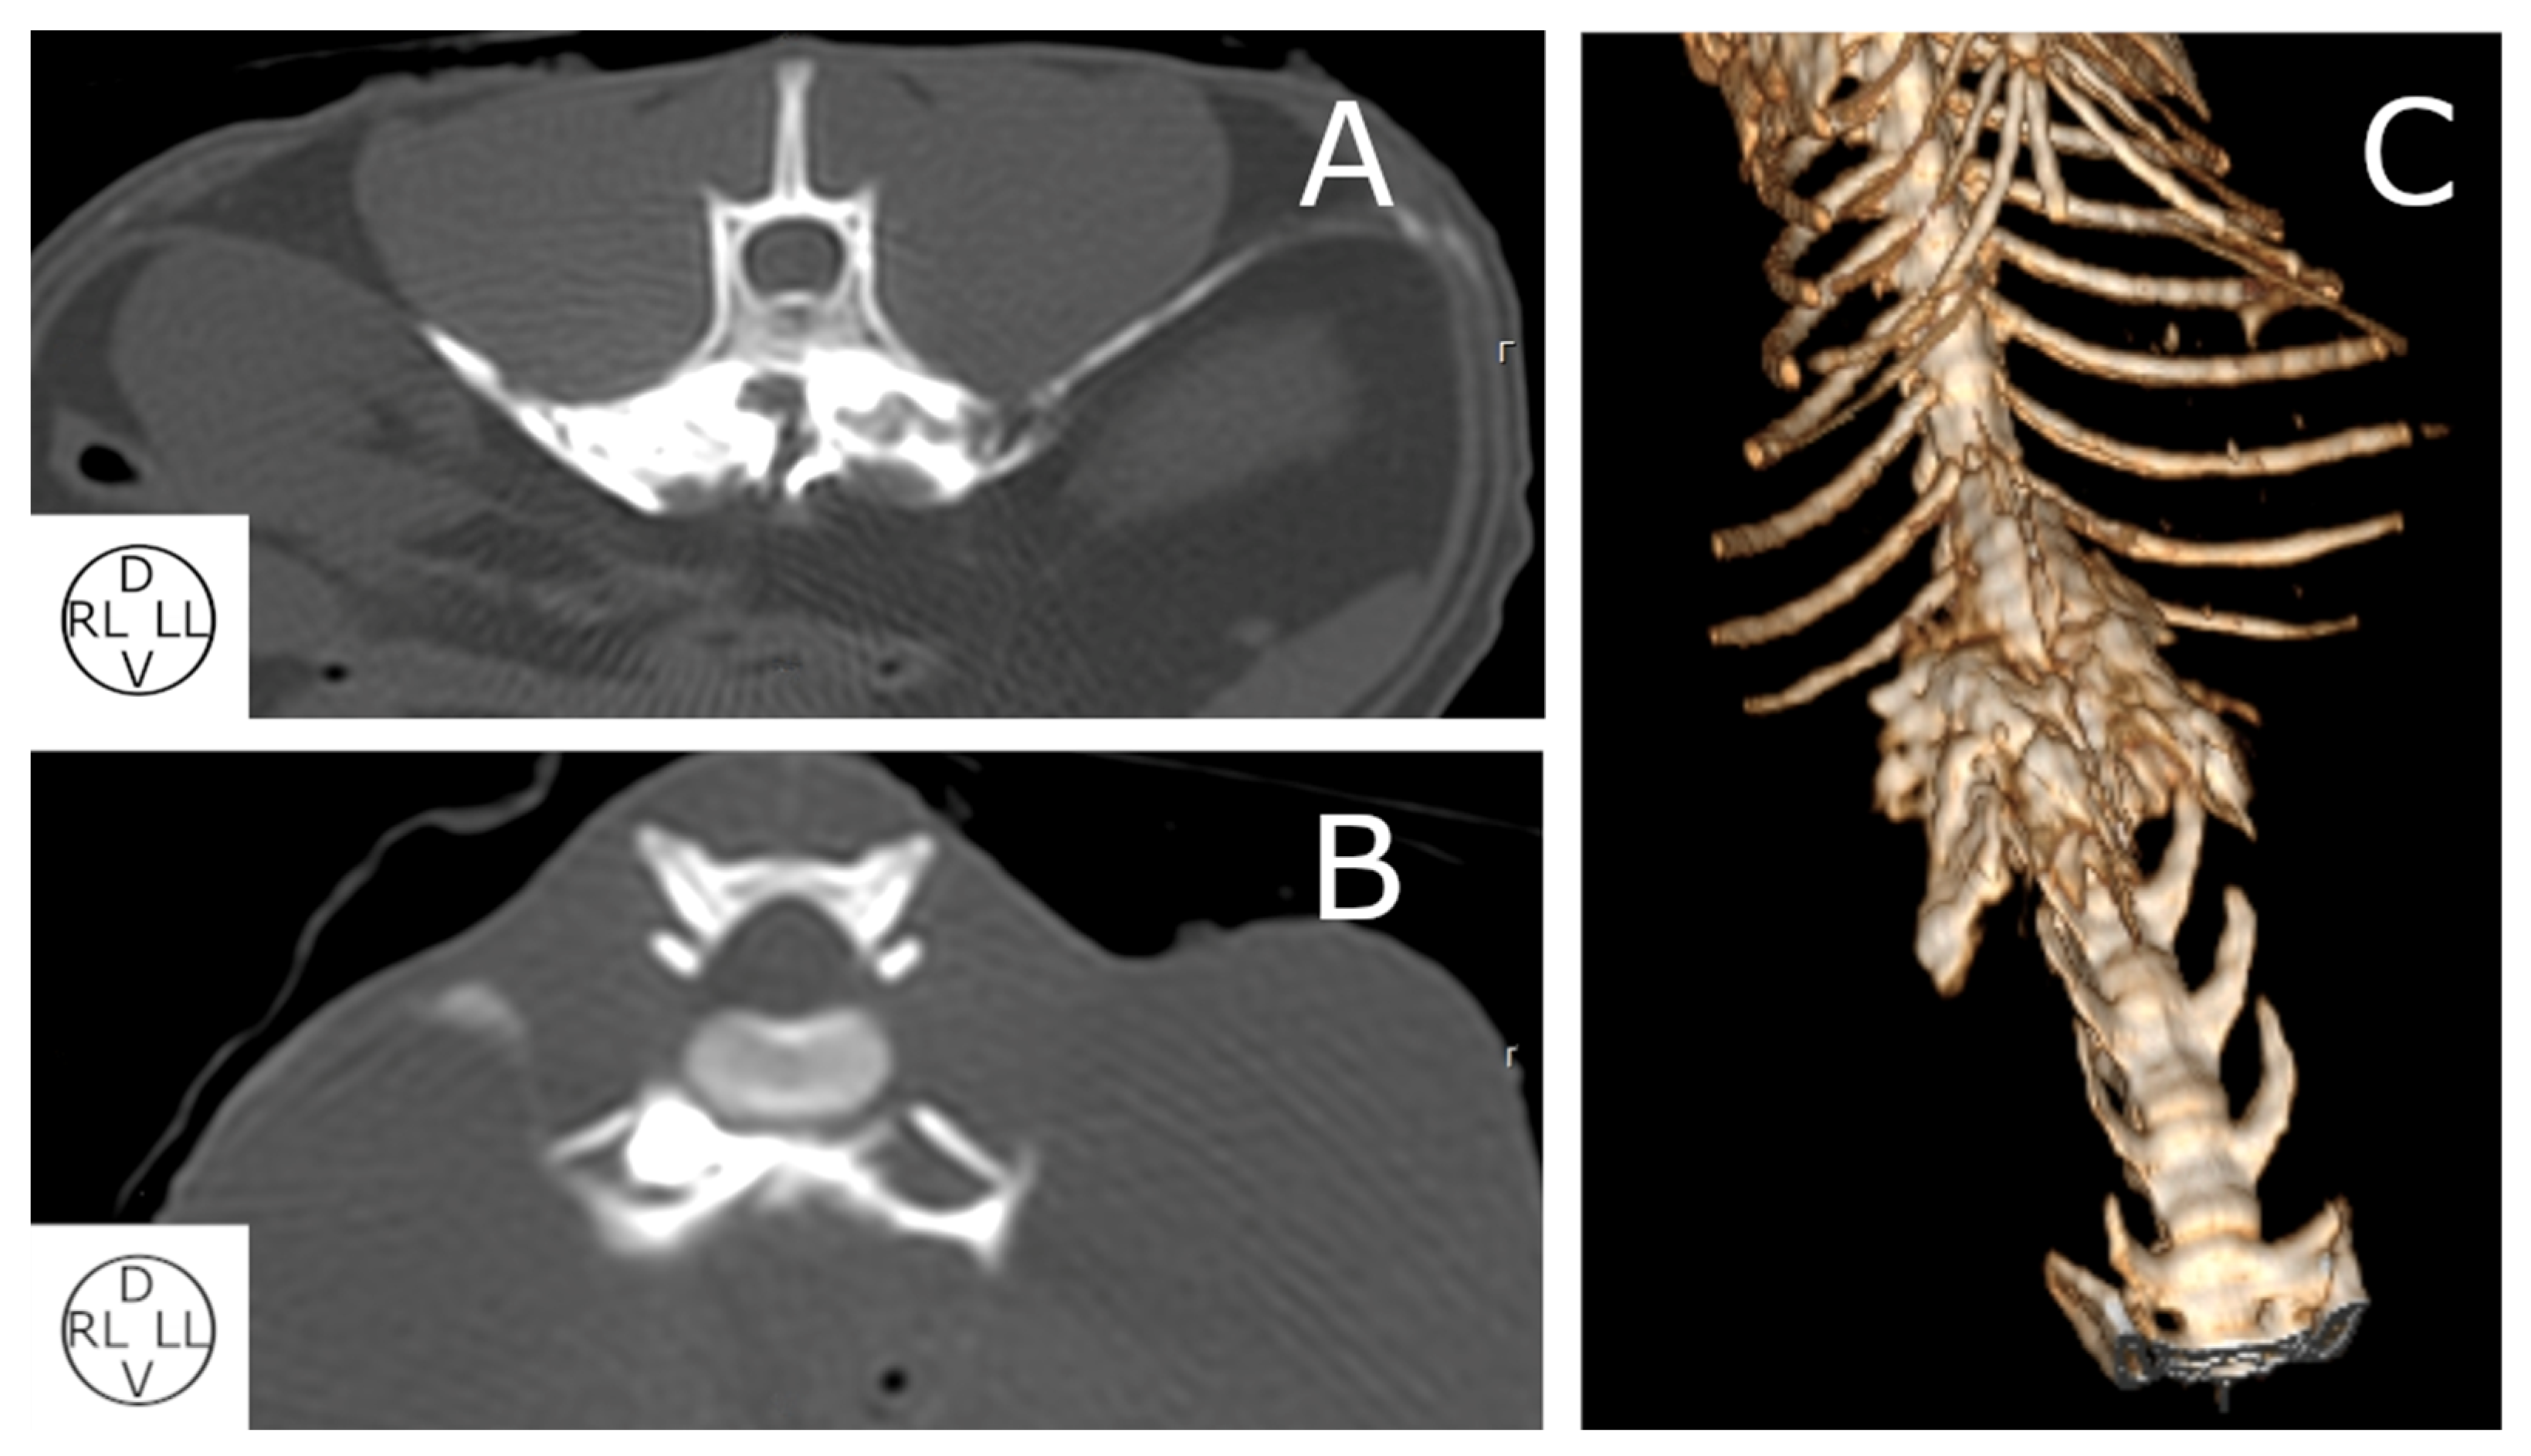

2.2.2. Computed Tomography (CT) Study

2.2.3. Spread Study

3.2.3. Computed Tomography Study

3.2.4. Spread Study